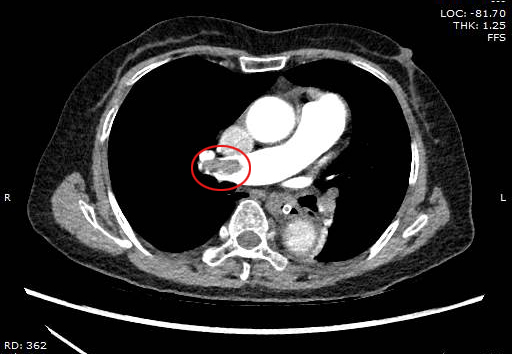

Hình ảnh chụp cắt lớp vi tính động mạch phổi bệnh nhân T. bị tắc do cục máu đông

Qua thăm khám lâm sàng và điện tâm đồ, nghi ngờ bệnh nhân bị tắc động mạch phổi cấp, các bác sỹ đã ngay lập tức chỉ định thực hiện siêu âm tim thấy tình trạng giãn thất phải, có tăng áp lực động mạch phổi. Để chẩn đoán xác định, các bác sỹ tiếp tục chỉ định chụp cắt lớp vi tính động mạch phổi, kết quả trên phim chụp cắt lớp vi tính cho thấy bệnh nhân bị tắc động mạch phổi cả 2 bên, lâm sàng bệnh nhân diễn biến xấu hơn, đau ngực nhiều, khó thở, huyết áp tụt 80/60mmHg.